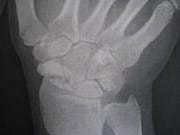

リハビリも順調に進んでいまして、手首が上側20度、下側10度の

可動ができる様になりました!と、言っても日常生活レベルではまだまだの状態です。

1枚目オペ前日 2枚目オペ直後 3枚目昨日 いかがですか?

骨の写真ばっかりですみません(汗)